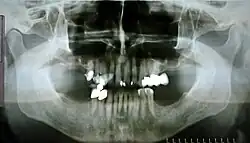

Medizin

Als Panoramaaufnahmen oder Orthopantomogramme werden auch „Panoramaröntgenbilder“ in der zahnärztlichen Praxis bezeichnet. Hierbei wird ein Komplettröntgenbild des gesamten Ober- und Unterkieferbereiches einschließlich der Kiefergelenke und der Nebenhöhlen erstellt.